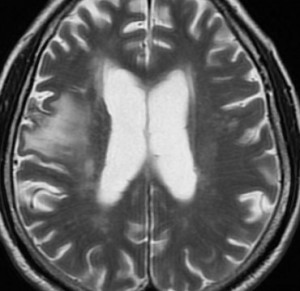

60代後半の患者さんで右前頭葉転移性脳腫瘍です。けいれん発作で発症しました。

定位放射線治療前

典型的な脳転移のMRIです。腫瘍は,リング状にガドリニウム増強され,内部が腫瘍壊死になっています。腫瘍周囲の脳浮腫がとても強いのが転移の特徴的画像所見(右側のT2強調画像)です。この転移巣に対して,35グレイ・5分割の定位放射線治療が加えられました。